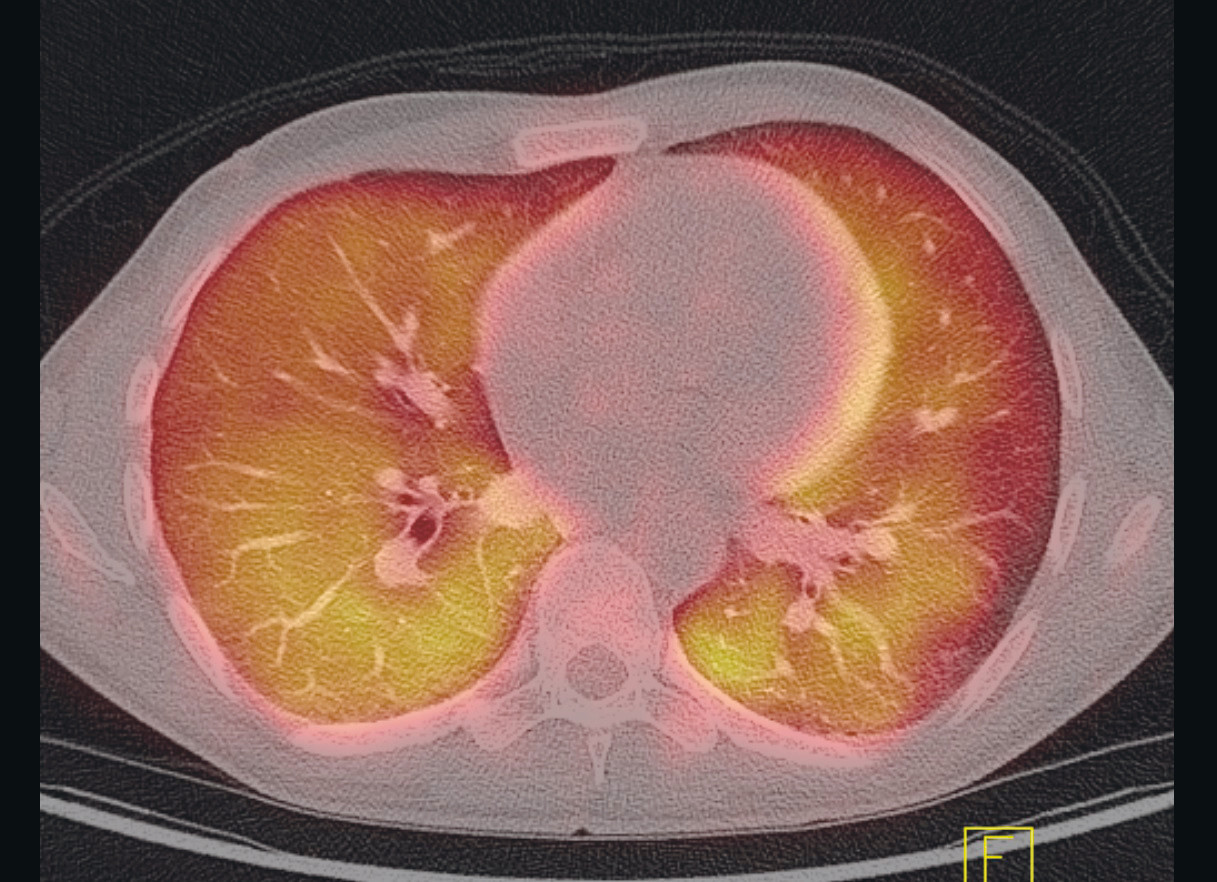

In the days that followed, the patient continued to have episodes of fever and increasing dyspnoea, as well as reduced general condition. PET-CT scan was performed, which showed signs of widespread, diffuse uptake of ¹⁸F-fluorodeoxyglucose (¹⁸F-FDG) in both lungs, as well as reactive spleen and bone marrow (Figure 1).

PET-CT is a modality that combines PET and multislice CT. The most common marker is radioactive ¹⁸F-FDG, a glucose analogue that functions as a marker for metabolic activity in tissue. The PET detector records where the ionising radiation is concentrated in the body, and this is correlated with the anatomic structures on the CT images. Increased ¹⁸F-FDG uptake on PET-CT may be seen, for example, with increased cell division in malignant tumours, and with increased activity in leukocytes in the case of infections and non-infectious inflammatory disorders.